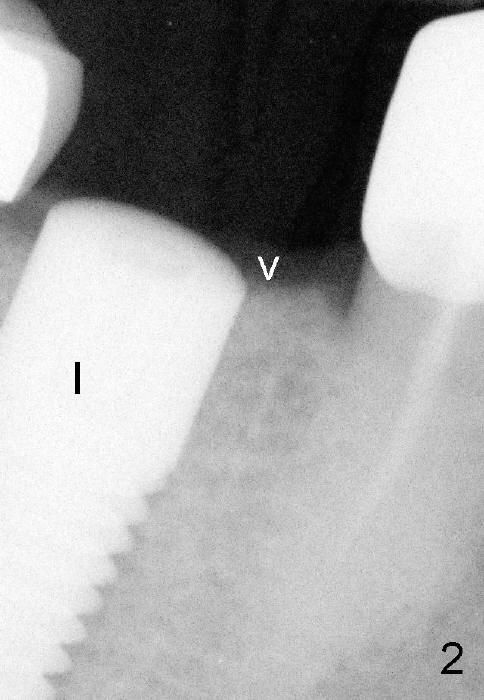

六十三岁台湾太太两年前右下第一磨牙准备做植牙,术前X光片显示缺牙区近中牙槽脊骨质好像有些特殊(图一箭头)。六乘十七毫米植牙(I)刚植入(图二,做了bone expansion),近中骨质好像又没有问题(箭头)。六个月后植牙近中骨质游离(图三箭头),除去骨片后,牙龈愈合,一个月后戴上牙冠(图四C),近中骨质仿佛没有异常。一年半后,病人突然回诊所,抱怨植牙周围流出臭味水,有些压痛。检查发现牙冠近中有个瘘道(图六箭头),下面好像有游离骨片,植牙牢靠,根尖片显示近中上部骨质稀疏(图五*),游离骨片(箭头)。翻开牙龈,除去相当大游离骨片,植牙粗糙面暴露(图七*,原有游离骨片所在地),除去炎性肉芽组织(+ +)后,植牙上部一两个螺纹暴露,箭头表示骨缺损边缘。反复用生理盐水冲洗,然后稀释四环素溶液冲洗,用探针和curet轻轻刮除植牙表面和螺纹菌斑,涂Straumann PrefGel,又用生理盐水冲洗,涂Endogain,植入Rocky Mountain Irradiated Allogenic Cancellous Bone and Marrow (图八*)。沐旭生医生认为植骨可能不管用,细菌很难清除,最好拔除植牙,植骨,然后再植牙。病人自己也意识到这个可能性,现在只有希望奇迹出现:缺损太大,不植骨身体可能无法修复。